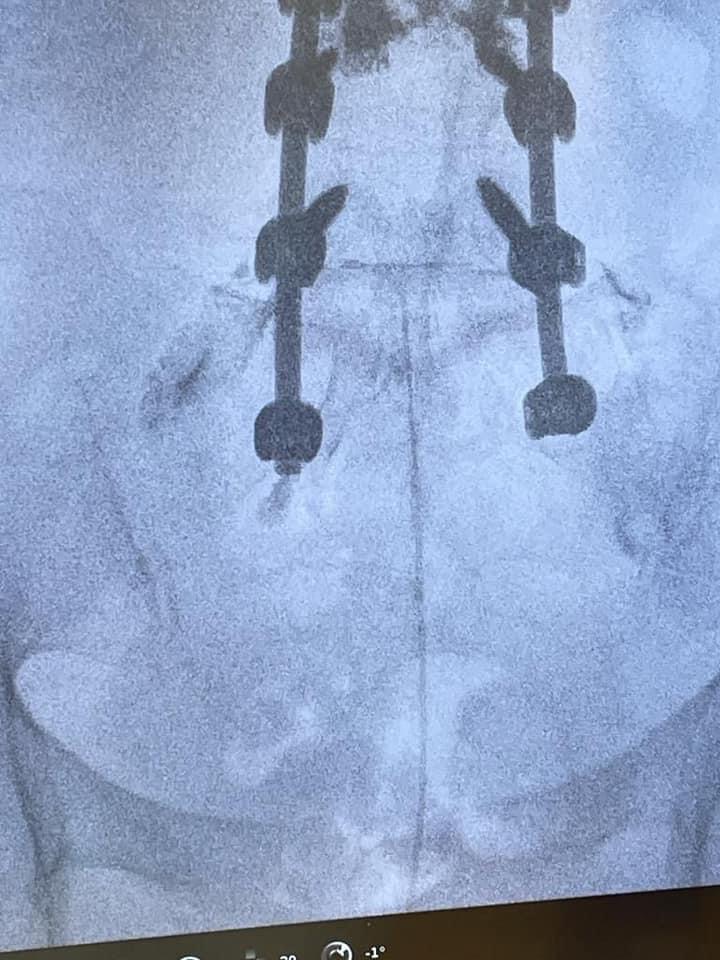

Mario, 50 anni, soffre da anni di mal di schiena lombare con irradiazione agli arti inferiori (lombosciatalgia). Mario negli anni passati è stato sottoposto a due interventi chirurgici alla schiena: 1) asportazione dell’ernia (discectomia), 2) stabilizzazione vertebrale. Nonostante questi due interventi Mario non ha risolto il suo problema, anzi la sintomatologia è peggiorata, per cui si rivolge al dottore Lo Bianco. Dopo un’attenta valutazione dell’imaging radiologico (risonanza magnetica lombare), dello studio elettromiografico ed una accurata visita specialistica, il dottore Lo Bianco propone un intervento di epidurolisi presso lo studio di Palermo. È una procedura mininvasiva che prevede, sotto guida fluoroscopica e dopo anestesia locale o blanda sedazione, l’introduzione di un catetere che, attraverso una lisi meccanica e farmacologica, permette lo sbrigliamento delle radici nervose compresse o stirate da cicatrici chirurgiche, riducendo così la sintomatologia dolorosa.

Il Dr. Giuliano Lo Bianco effettua trattamenti di epidurolisi a Palermo presso lo studio privato in Via Ugdulena, 30, e presso il Giglio Hospital a Cefalù. È una procedura mini invasiva che prevede, sotto guida fluoroscopica e dopo anestesia locale o blanda sedazione, l’introduzione di un catetere/elettrodo che attraverso una lisi meccanica e farmacologica, permette lo sbrigliamento delle radici nervose compresse o stirate, riducendo così la sintomatologia dolorosa.